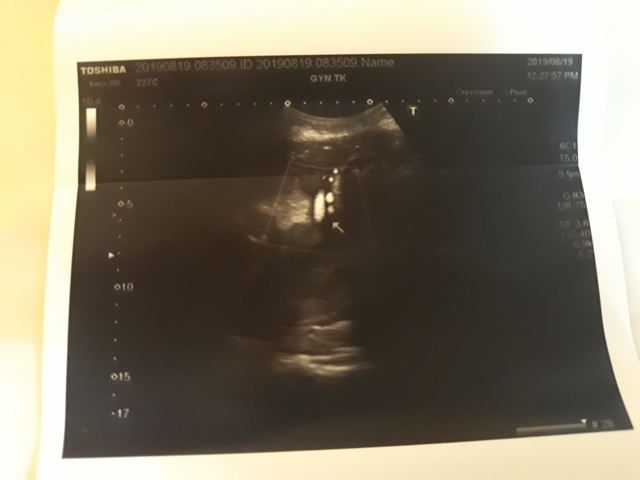

當小純進入診間看診時,我並沒有進去,因為小純說,有時男生不能進去,會被請出來。在外頭等待的我感到很緊張,不久之後,謢理人員請我進入診間,我嚇了一跳,想說發生什麼事了,進入之後,得知小純真的懷孕了,而且已懷了九星期又五天。看診的醫師說,驗孕棒第二條線淡淡的,沒想到胚胎照出來那麼大了,說Baby很健康。還說一閃一閃的是他的心跳,有頭、有手、有腳還有臍帶。小純後來說看了內心覺得很感動,才叫我一起進去看。

小純肚子裡的Baby超音波圖↓